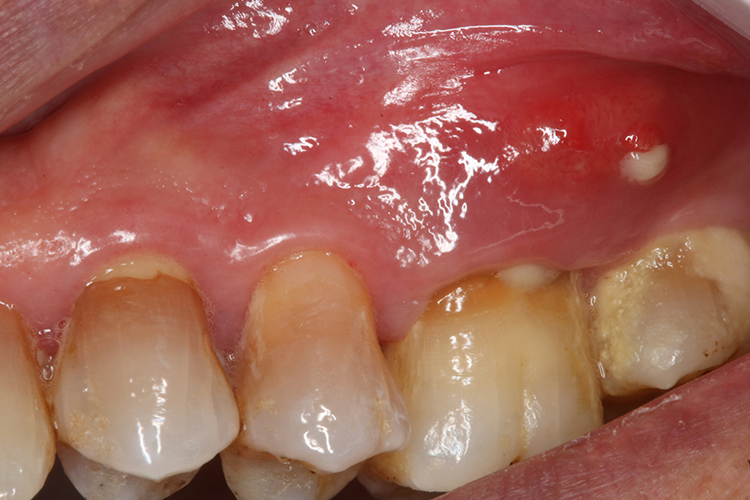

牙龈瘘管:部分牙齿的牙根较长,其根尖在颌骨内的位置较深,且超过口腔前庭沟,脓液易穿通较薄的骨壁至黏膜下,突破黏膜而形成相应部位的窦道,开口于黏膜表面的窦道多表现为黄豆大小的肉芽肿样,造成牙龈上有白泡的情况。